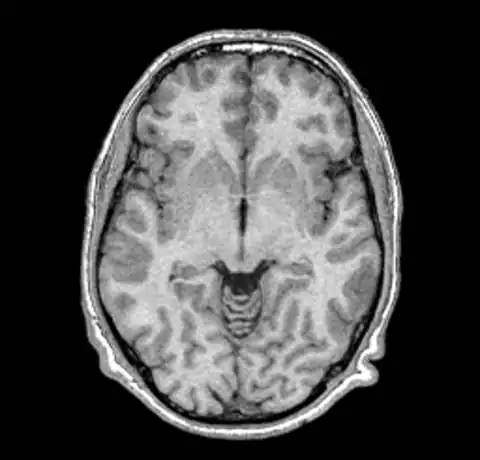

B0 non-uniformity is difficult to detect when simply looking at images without the assistance of a judiciously ranged color map. In our test case we'll start with a simple T1 MPRAGE image from a 1.5T Siemens scanner.

The above image and all the images here were created using mincpik in a similar fashion to the below.

Note that it is difficult to pick the non-uniformity in the image unless you look carefully at the intensity of the white matter in the lower parts of the image. In order to correct this image we run nu_correct with the default parameters.

We can now take a look at the corrected file (out.mnc)

As it is very hard to pick the differences between the original and corrected version we can create a field image to visualise the differences.

And then for completeness sake, here are the original and corrected image using a spectral colormap to better visualise the change. Note that in the second (corrected) image the intensity of the white matter is more uniform (the red part).